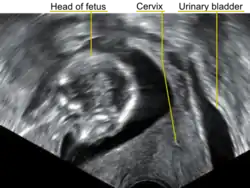

In a pregnant woman who is entering her second trimester, the combination of urinary difficulties and pelvic pain may alert the physician to consider uterine incarceration as a possibility. On physical examination, the cervix is pushed up and anterior, and the pelvis entirely filled by the soft mass of the body of the pregnant uterus. Sonography may indicate the retroverted position of the uterus, check on the viability of the fetus, and demonstrate the location of the bladder being pushed cranially and unable to be emptied.[4] Also magnetic resonance imaging has been found to be helpful in the diagnosis of the condition.[4][5]